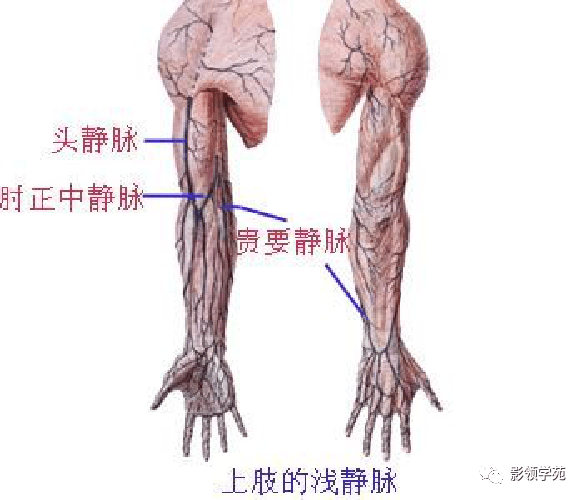

手臂动脉走向

前臂动脉走向

手臂动脉走向

前臂动脉走向